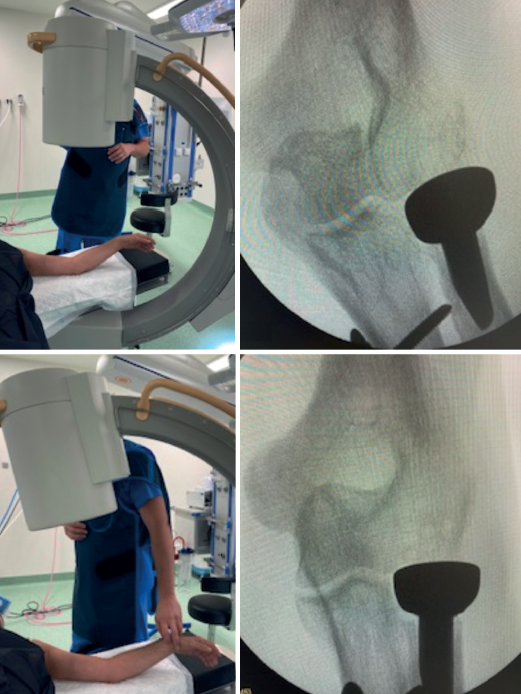

Tanto la rigidez como la inestabilidad pueden estar directamente relacionadas con una elección inadecuada del implante o una mala posición de este(3,4). La literatura anglosajona utiliza el término overstuffing para referirse a la sobrecarga que ejerce la prótesis sobre el capitellum, que puede ocurrir por un exceso de diámetro del implante (se recomienda usar 1 mm menos que la cabeza retirada) o por un exceso de longitud (debe quedar a la altura del margen lateral de la apófisis coronoides, por lo que ha de comprobarse intraoperatoriamente mediante radiología). El término overlengthening es más adecuado para referirse a la mala posición del implante por exceso de longitud(5), consecuencia de una altura de resección insuficiente. Una menor área de contacto entre la prótesis y el capitellum, así como un diferente módulo de elasticidad, justifican la aparición de erosión en el capitellum. La presión entre la cabeza protésica y el capitellum se incrementa notablemente por encima de 2 mm de exceso de longitud(5). Para valorar correctamente la posición de la prótesis, hay que tener en cuenta el déficit de extensión, angulando el rayo de modo que este sea ortogonal al antebrazo y no al húmero distal (Figura 1).